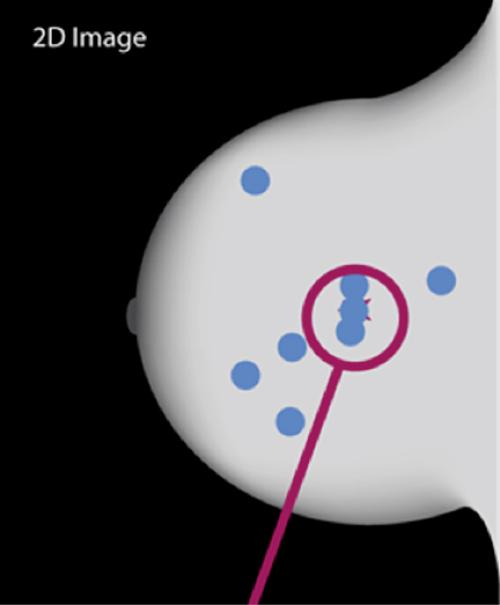

Image

Normal breast tissue may mimic an abnormality due to overlap, resulting in a false positive test and a call back for additional testing.

A small cancer is masked by the normal breast tissue resulting in a false negative interpretation.